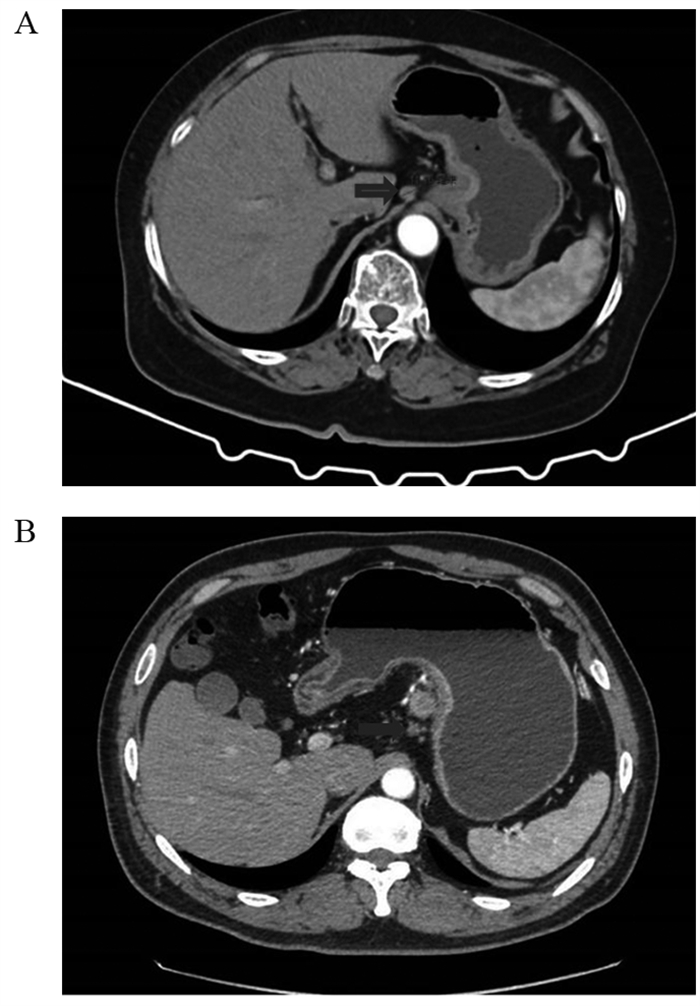

方法回顾性分析268例胃癌患者的临床病理资料。患者术前常规行薄层增强CT评估术前N分期,结合术后病理结果分析术前N分期不足的危险因素。Logistic回归分析筛选出的影响因素,Kaplan-Meier绘制术前N分期准确组与不足组的生存曲线,利用R软件包绘制Nomogram图、预测模型的ROC曲线,计算AUC、95%CI、敏感度和特异性。

MethodsA retrospective method was used to analyze the clinicopathological data of 268 patients with gastric cancer. The patients routinely underwent preoperative thin-section enhanced CT to assess preoperative N-stage. Results The risk factors for preoperative N-stage deficiency were analyzed in combination with postoperative pathological findings. Multifactorial logistic regression analysis was performed to determine influencing factors, and Kaplan-Meier analysis was used to plot the survival curves of preoperative N-stage accurate group and deficiency group. The nomogram plot and ROC curves of the prediction model were drawn using the R package. AUC, 95%CI, sensitivity, and specificity were calculated.